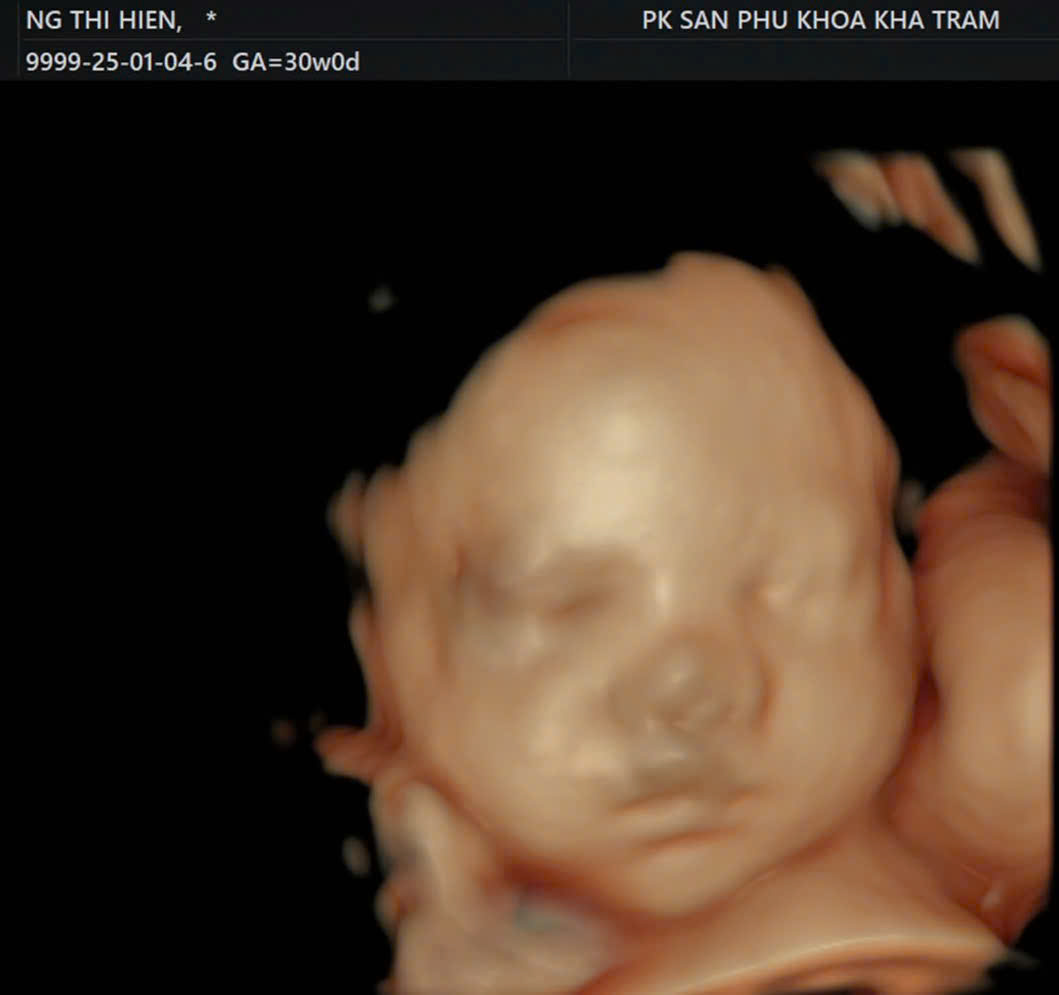

Siêu âm thai đánh giá tăng trưởng thai từ 30 tuần đến 32 tuần

Giai đoạn tam cá nguyệt thứ ba là thời điểm quan trọng để theo dõi sự phát triển toàn diện của thai nhi và phát hiện sớm các biến chứng cuối thai kỳ.